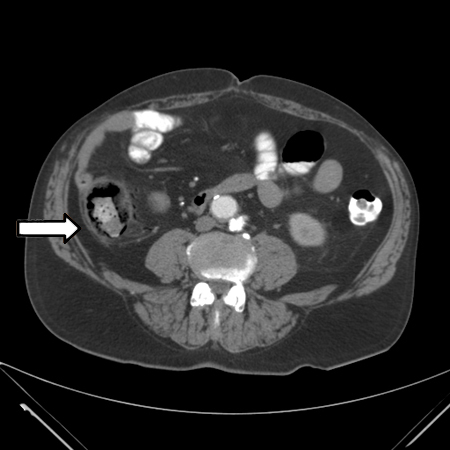

Considere uma angiotomografia precoce em um paciente com dor abdominal e acidose láctica.[8] A angiotomografia substituiu a angiografia convencional como prática padrão para avaliação da vasculatura mesentérica e diagnóstico de isquemia mesentérica aguda.[30] Ela pode ser usada no diagnóstico de uma isquemia mesentérica não oclusiva (IMNO).[43] A angiotomografia também pode fornecer informações para ajudar a decidir sobre a modalidade do tratamento, como o reparo endovascular.

[Figure caption and citation for the preceding image starts]: Angiotomografia: trombo agudo da artéria mesentérica superiorDo acervo da Dra. Jennifer Holder-Murray; usado com permissão [Citation ends].

[Figure caption and citation for the preceding image starts]: Angiotomografia: reconstrução tridimensional com estenose da artéria mesentérica superior devida a placa arteriosclerótica grave em um paciente submetido a imagens de acompanhamento após reparo de aneurisma endovascularDo acervo da Dra. Jennifer Holder-Murray; usado com permissão [Citation ends].